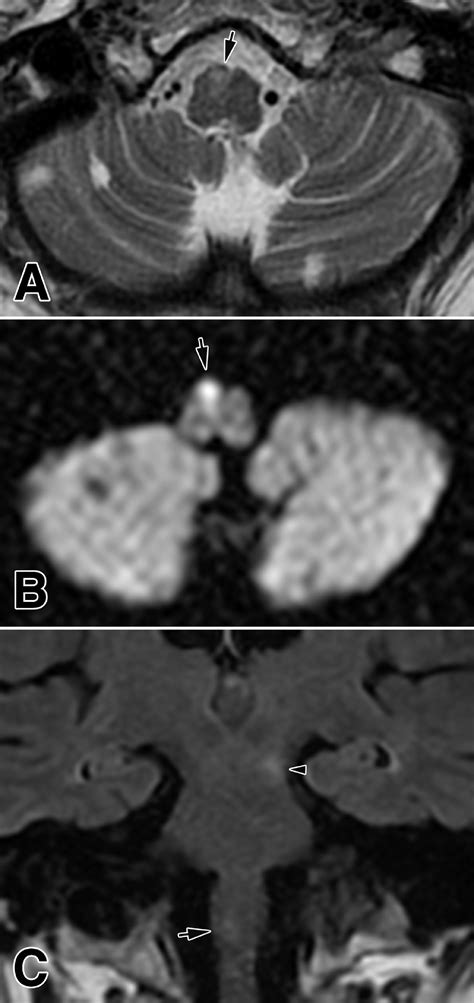

To confirm a Lateral Medullary Stroke, physicians rely on advanced imaging techniques. While a CT scan is often the first line of defense to rule out hemorrhage, it is frequently insensitive to small strokes in the brainstem. Therefore, a diffusion-weighted MRI (DWI-MRI) is the gold standard for visualization.

MRI (Magnetic Resonance Imaging) Best for identifying infarctions in the brainstem tissue.